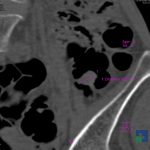

În cazul traumatismelor cranio-cerebrale:

- Diagnosticul edemului cerebral, a contuziei cerebrale, a leziunilor axonale difuze edematoase/hemoragice, a dilacerării cerebrale, a hematomului intraparenchimatos posttraumatic, a hematoamelor subdurale/extradurale (acute, subacute, cronice), a hemoragiei intraventriculare, a hemoragiei subarahnoidiene

- Diagnosticul traumatismelor de bază de craniu